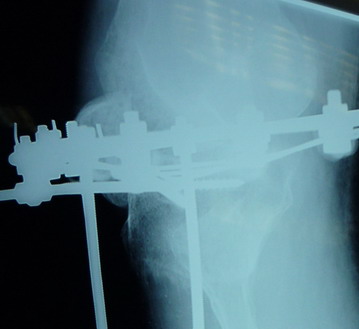

На последних рентгенограммах выявлено, что одновременно с "выращиванием" регенерата произошло низведение надколенника  на длину выращенного регенерата.

Клинически: активное разгибание сохранено, объем движений в колене 180-110 градусов.  Черными стрелками обозначен верхний край надколенника с одной и с другой стороны. Красная стрелка обозначает пальпируемую связку надколенника.

Причина - остеотомия выше места прикрепления связки надколенника.